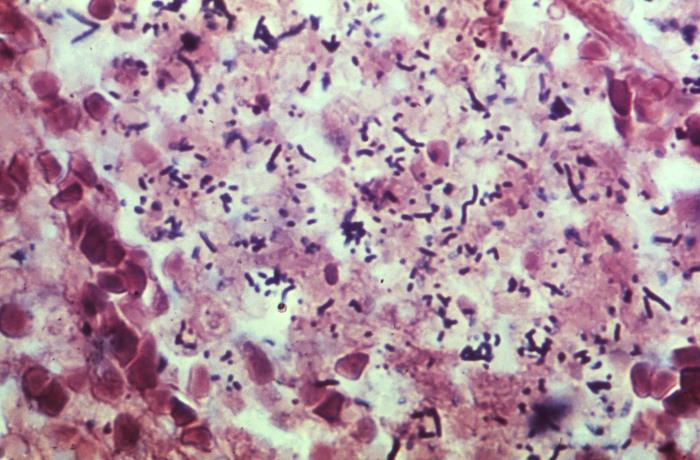

顯微鏡下的李斯特菌

生物顯微鏡下李斯特菌呈單個或短鏈狀

多數(shù)李斯特菌體***端較大,似棒狀

培養(yǎng)時間延長或粗糙型培養(yǎng)可呈絲狀菌體